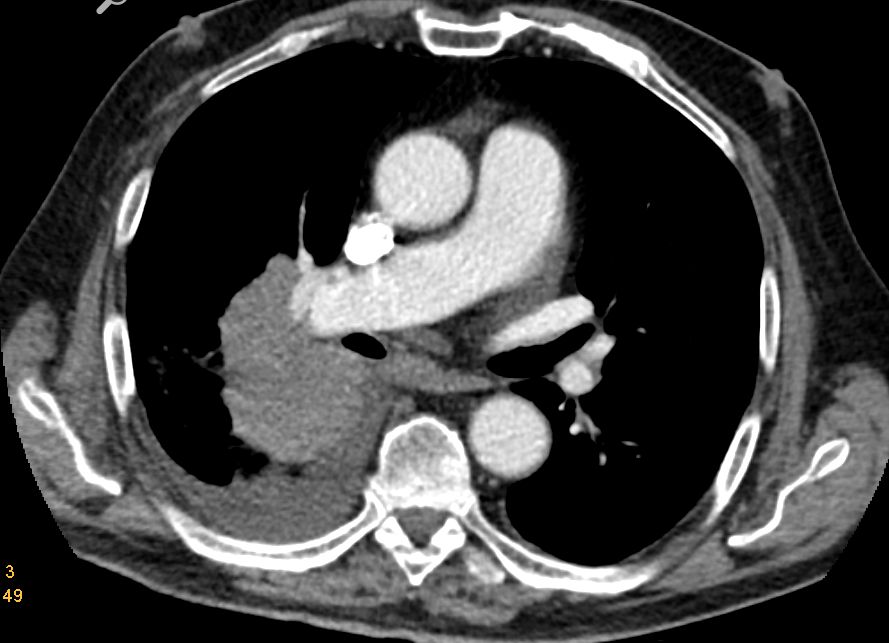

Nebennieren - Metastase

Links Nebennierenmetastase, Stauungsniere rechts, Ableitung links.